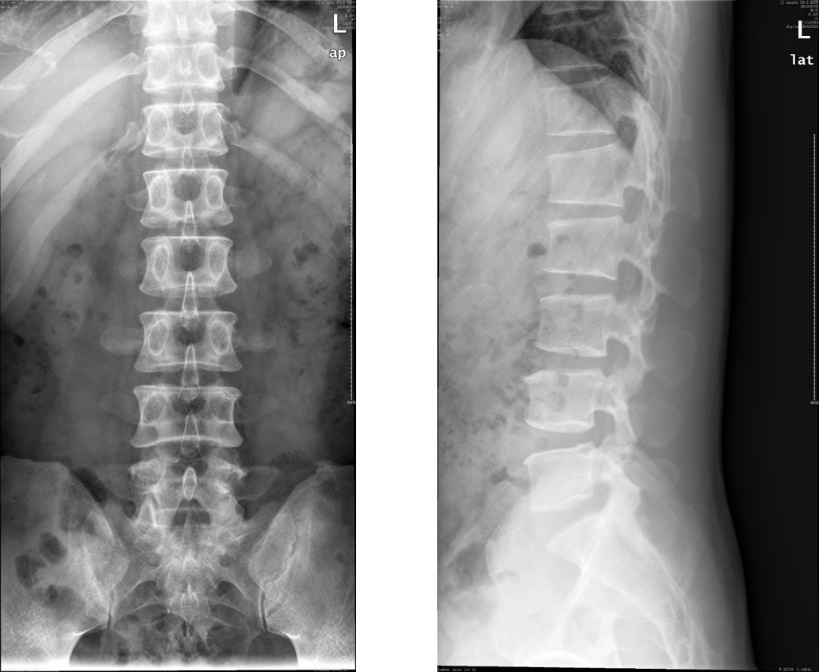

腰椎CTスキャンとは何ですか?

CT スキャン (一般に CAT スキャンと呼ばれます) は、体の特定の部分の断面画像を生成する X 線の一種です。

腰椎 CT スキャンの場合、医師は腰の断面図を見ることができます。スキャン機械が体の周囲を周回し、画像をコンピューターのモニターに送信し、そこで技術者が画像を検査します。

脊椎の腰椎部分は、背中の問題が発生しやすい領域です。腰椎は背骨の最も低い部分です。 5つの椎骨で構成されています。

腰椎の下には仙骨があり、仙骨の下には尾骨(尾骨)があります。大きな血管、神経、腱、靱帯、軟骨も腰椎の一部です。